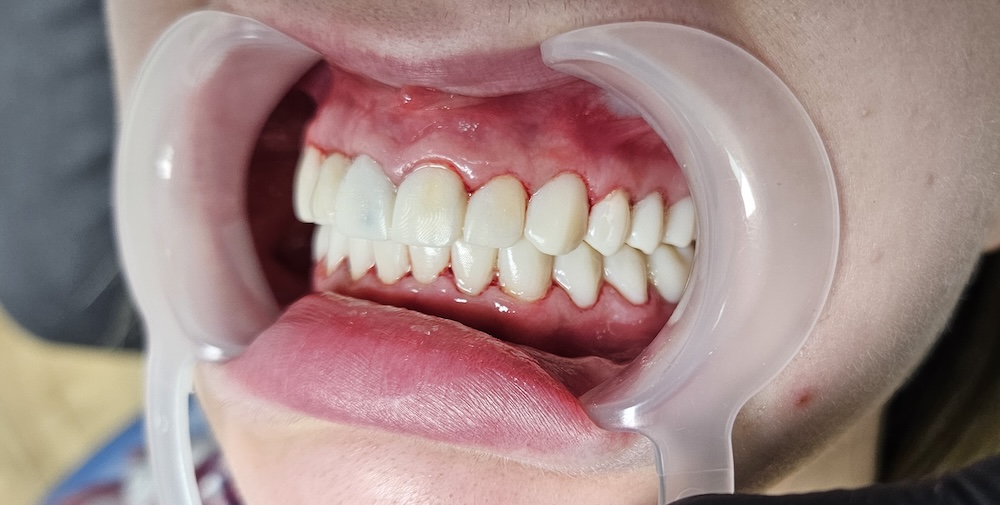

Коронки e.max

Через 7 днів зафіксували постійні керамічні коронки e.max — всього 28 коронок. Це вже не локальне лікування, а повна реконструкція усмішки, коли відновлюється не лише колір, а й анатомія зубів, їх форма і контакт між ними. На імплантах використали індивідуальні цирконієві абатменти — це проміжна частина між імплантом і коронкою. Вони дозволяють уникнути сірої тіні біля ясен і зробити результат максимально природним.